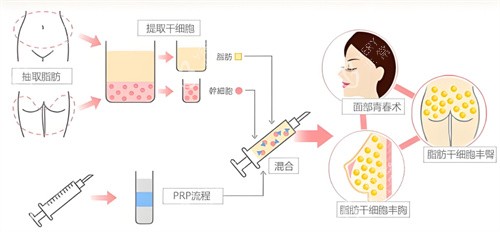

抽脂完成后,医生对抽取的脂肪进行了处理,将健康、有活力的脂肪筛选出来,准备注入乳房。接下来就是脂肪注射环节,医生小心翼翼地将处理好的脂肪一点一点注入乳房,调整乳房的形状和大小。手术持续了几个小时,结束后我被送回病房休息。

一般来说,脂肪的吸收率在30% - 70%左右,这受到多种因素的影响,比如个人体质、脂肪质量、手术操作等。我的体质可能对脂肪的吸收比较快,再加上手术过程中部分脂肪可能没有得到良好的血供,导致存活的脂肪数量有限,所以胸部增大的结果就不那么明显。